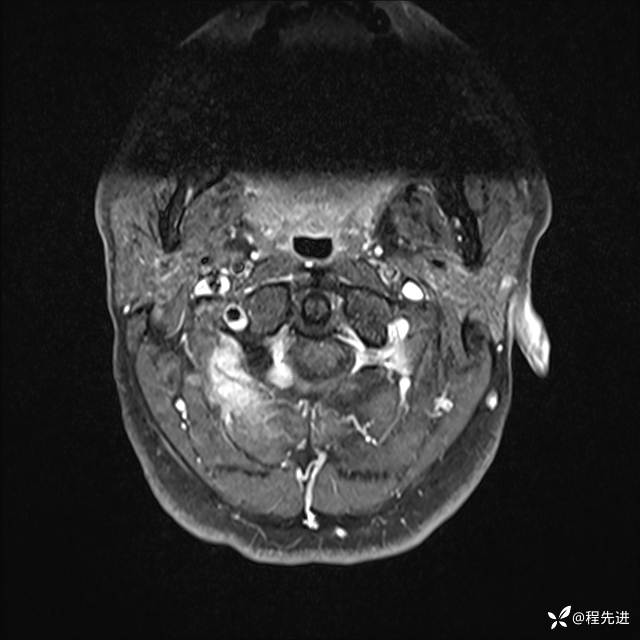

MRI平扫+增强:

T1增强: